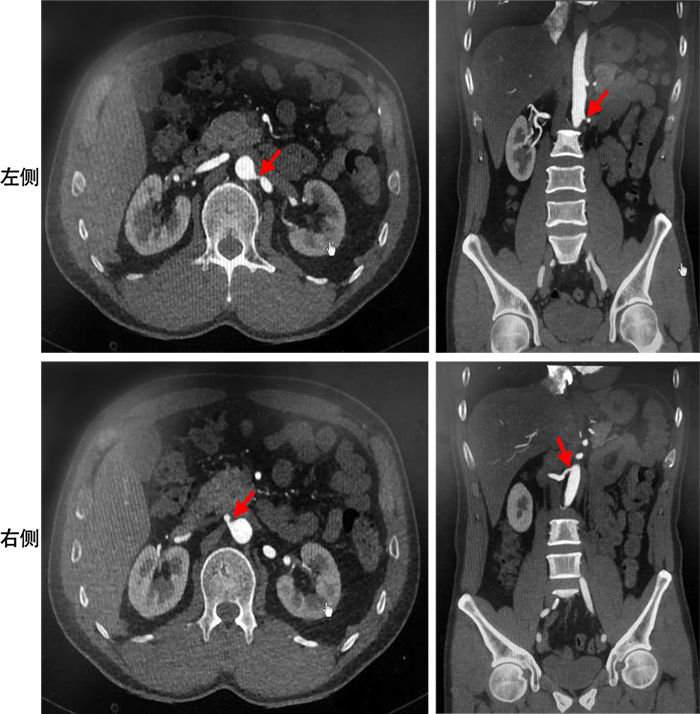

• 摘要: 由双侧肾动脉狭窄(RAS)所致的难治性高血压,发病率较低,临床诊治较为困难。首都医科大学宣武医院全科医学科收治1例48岁男性患者,近期出现严重的高血压病史。考虑患者的年龄及高血压的严重程度,笔者筛查了继发性高血压的常见原因,进一步行腹主动脉CT血管成像,提示双侧肾动脉开口处中-重度狭窄,为双侧肾动脉狭窄导致的难治性高血压。联合血管外科分期实施双侧肾动脉支架植入术,术后随访患者血压逐渐控制稳定。本文对该患者具体诊治经过进行回顾性分析,并复习相关文献。

• 图  1  腹主动脉CTA

Figure  1.  Abdominal Aortic CTA